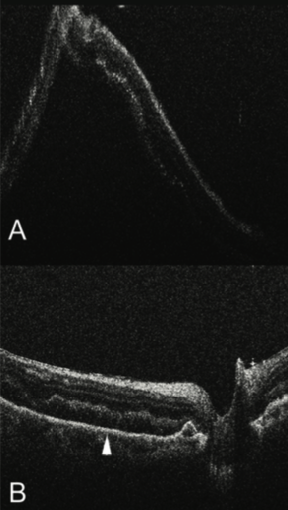

For example, perfluoro-n-octane (PFO) infusion during RRD repair appears to induce generalized blunting of the EZ junction and alterations in the foveal architecture, which have been associated with visual recovery in the postoperative period.24 In addition, subretinal fluid is frequently identified after PFO tamponade (Figure 3).8,14,24 These findings highlight yet another potential utility of intraoperative OCT: prognostication of vision outcomes following vitreoretinal interventions.

Figure 3. Intraoperative OCT during RRD repair showing bullous detached retina (A). Following perfluorocarbon liquid tamponade, the retina has significantly flattened, but persistent subretinal fluid remains (arrowhead, B).